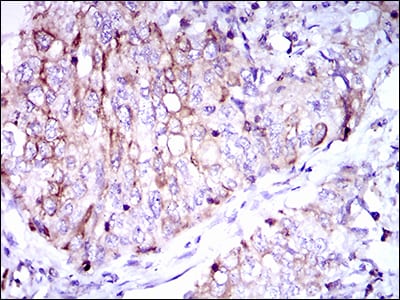

分类: 科研抗体货号: 30504别名: GSC应用: IHC,FCM反应种属: Human